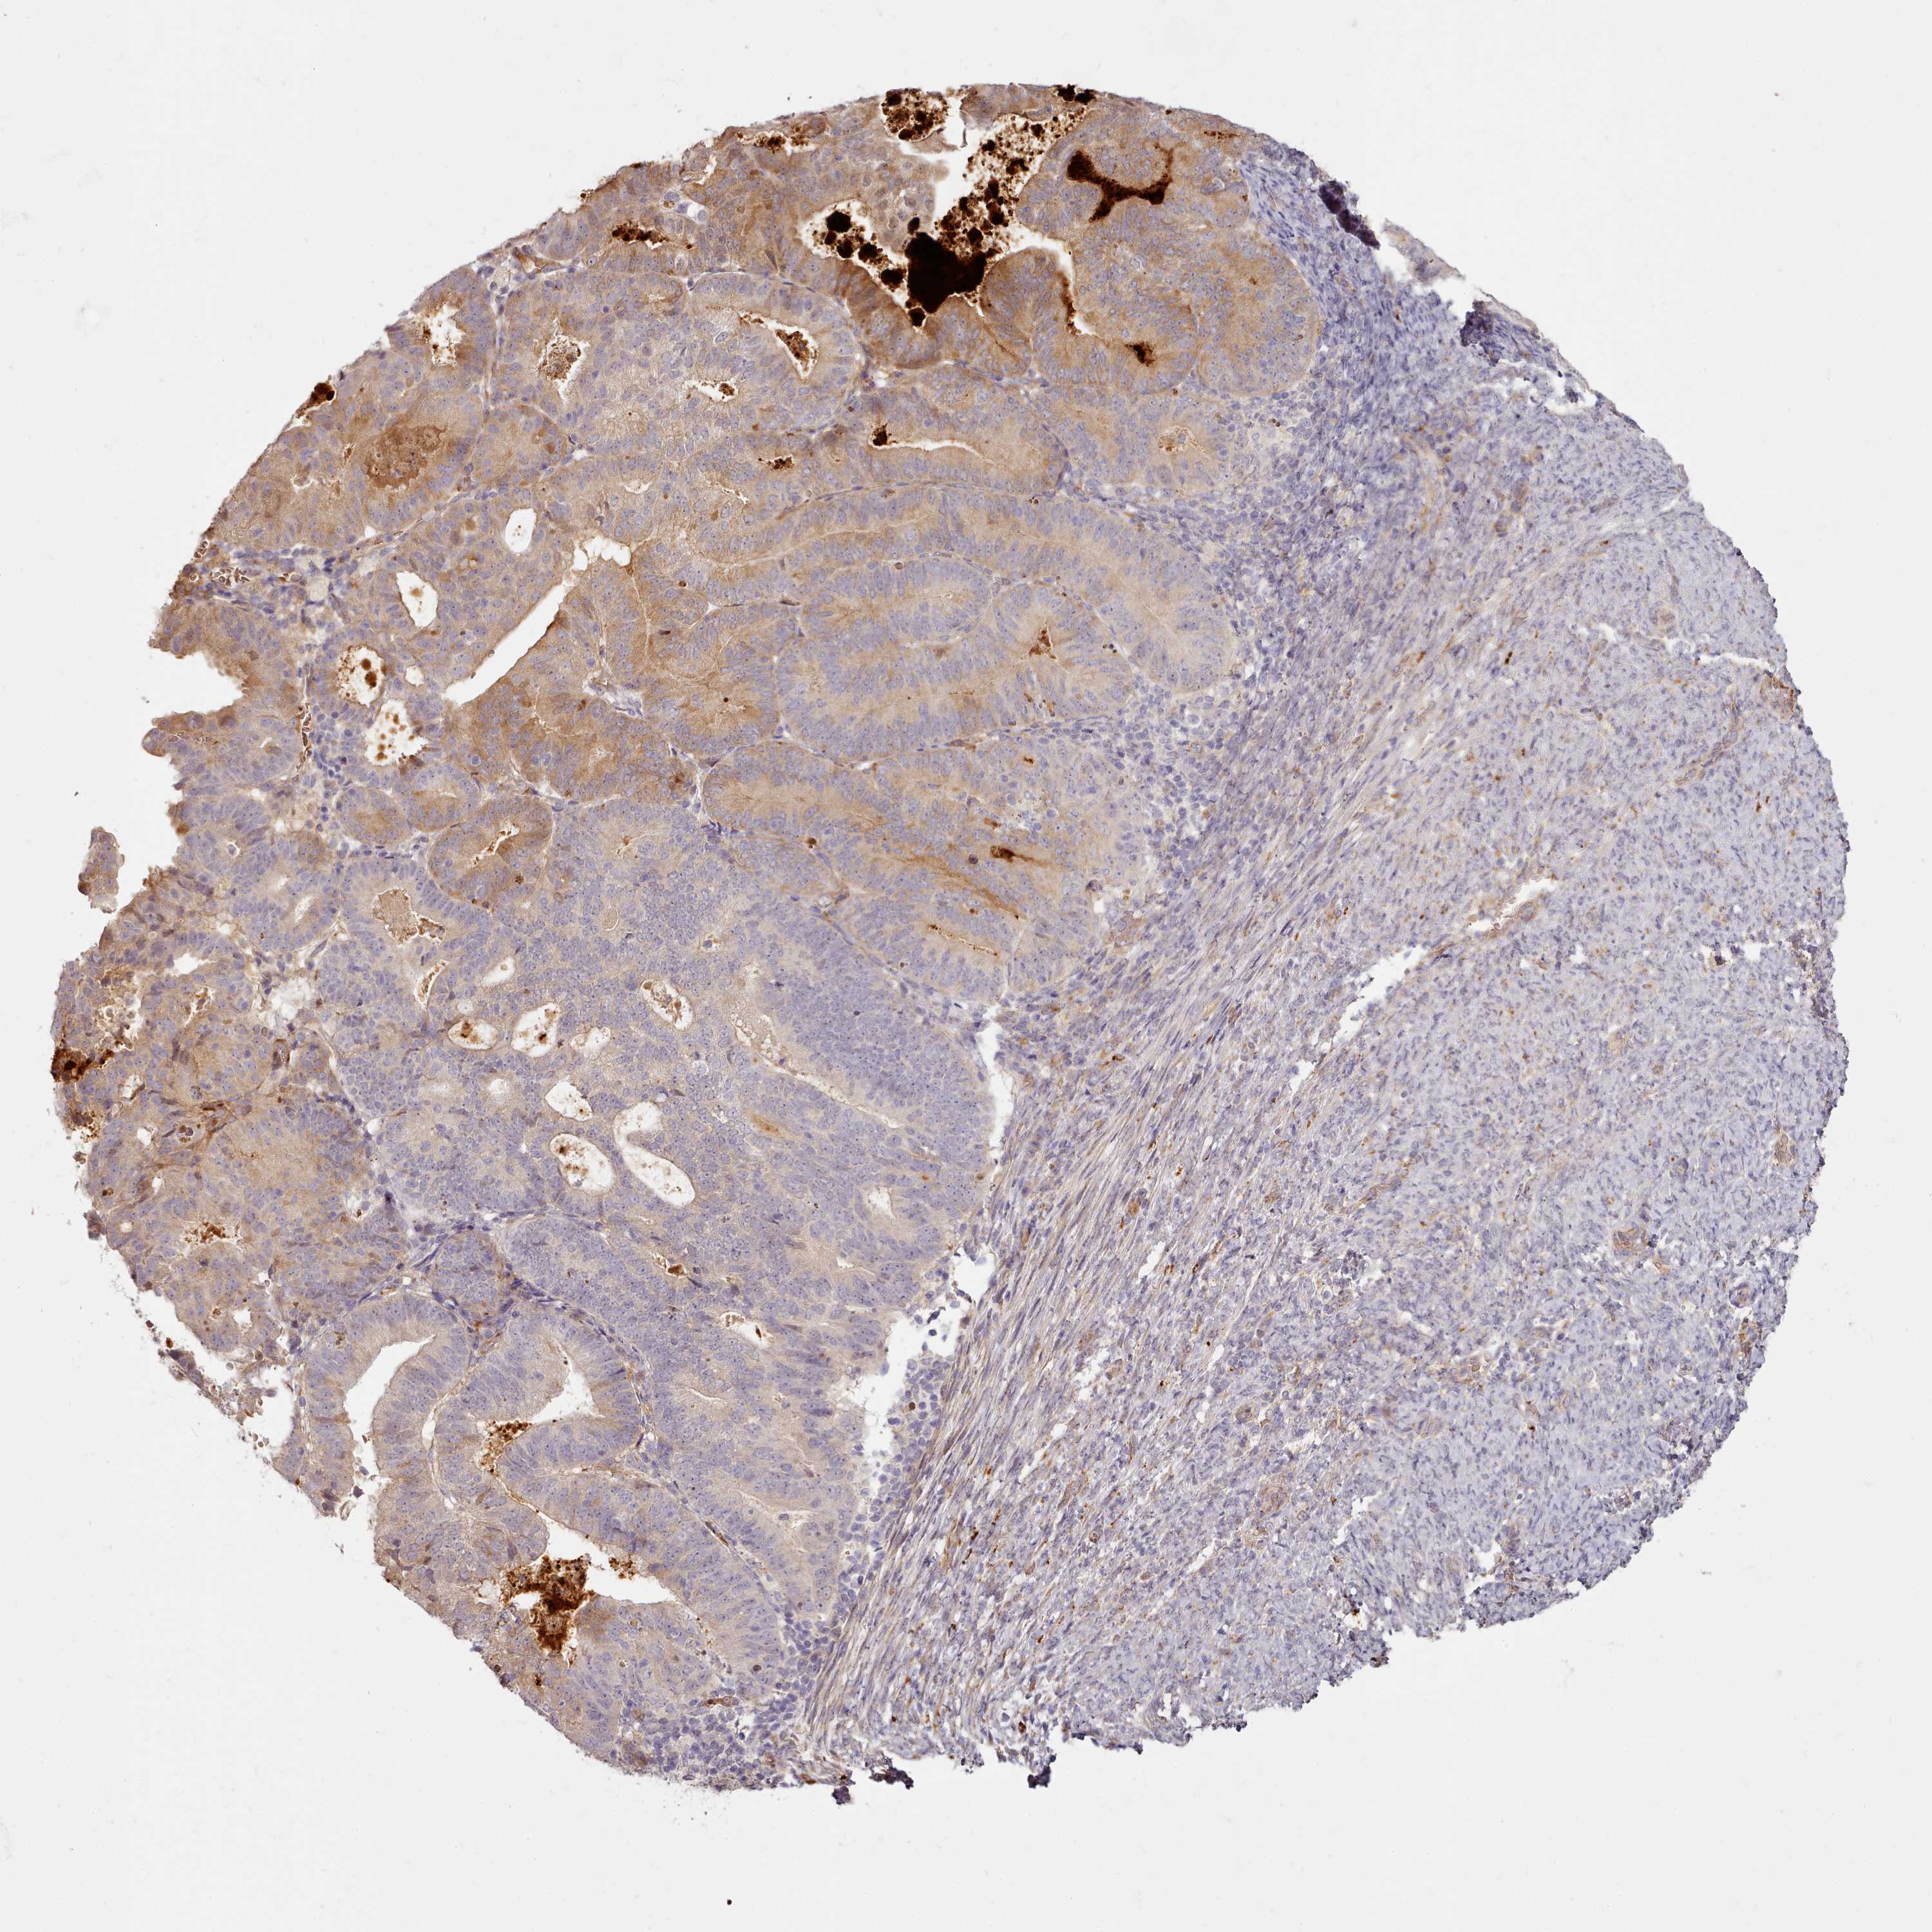

ENDOMETRIAL CANCER - Protein expressioni

A mouse-over function shows sample information and annotation data. Click on an image to view it in a full screen mode. Samples can be filtered based on level of antibody staining by selecting one or several of the following categories: high, medium, low and not detected. The assay and annotation is described here.

Note that samples used for immunohistochemistry by the Human Protein Atlas do not correspond to samples in the TCGA dataset.

Antibody stainingi

Antibody staining in the annotated cell types in the current human tissue is reported as not detected, low, medium, or high, based on conventional immunohistochemistry profiling in selected tissues. This score is based on the combination of the staining intensity and fraction of stained cells.

Each image is clickable and will lead to virtual microscopy that enables deeper exploration of all samples and also displays staining intensity scores, fraction scores and subcellular localization as well as patient and tissue information for each sample.

Antibody HPA038604

Antibody CAB025607

Staining

High

Medium

Low

Not detected

Intensity

Strong

Moderate

Weak

Negative

Quantity

>75%

75%-25%

<25%

None

Location

Nuclear

Cytoplasmic/membranous

Cytoplasmic/membranous,nuclear

Adenocarcinoma, NOS